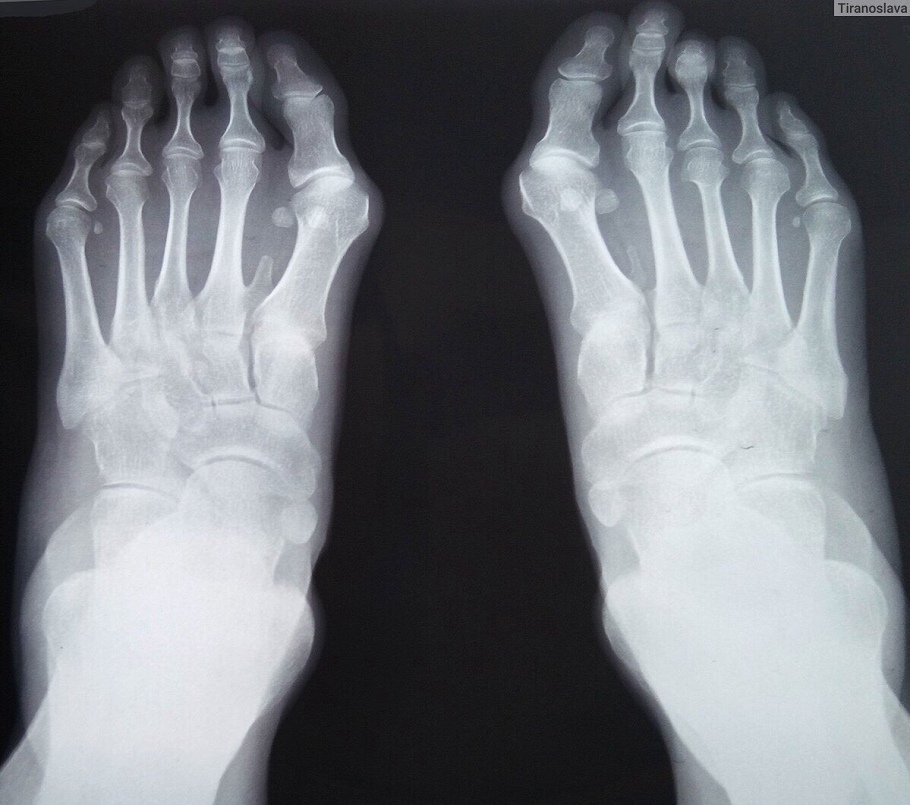

Фотографии и схемы патогенеза Халюс вальгуса